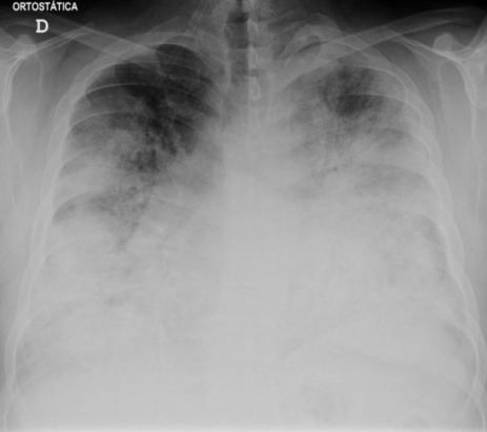

Legionnaires’ disease, a severe form of pneumonia named after the Legionella bacteria, has struck Manhattan. An outbreak affecting five ZIP codes in Harlem–10027, 10030, 10035, 10037, and 10039–began on July 25, and has infected 22 people as of July 31. One unidentified person has died.

Patients contract the disease via infected water vapor; it is not contagious. The “flu-like symptoms” referred to by the Health Department may include chest pain, fever, and a cough. It is treated with antibiotics, with earlier treatment producing better outcomes; the CDC advises that hospitals treat patients with azithromycin or levofloxacin.